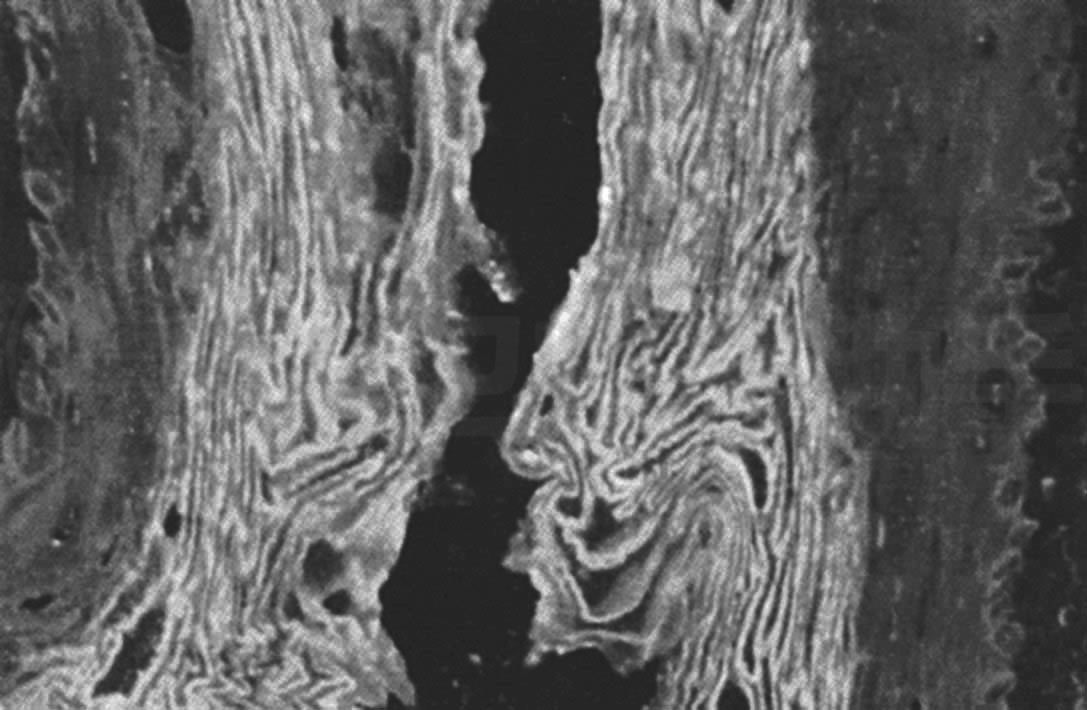

抗角蛋白抗体(anti keratin antibody,AKA)是针对人类表皮的丝集蛋白(filaggrin)的自身抗体,其易与食管角质层蛋白及上皮层的角质基底层蛋白和角质棘层蛋白发生反应,故以大鼠食管黏膜作为标准检测基质进行检测(图14-5)。

Fig. 14-5 Positive diagram of anti-keratin antibody